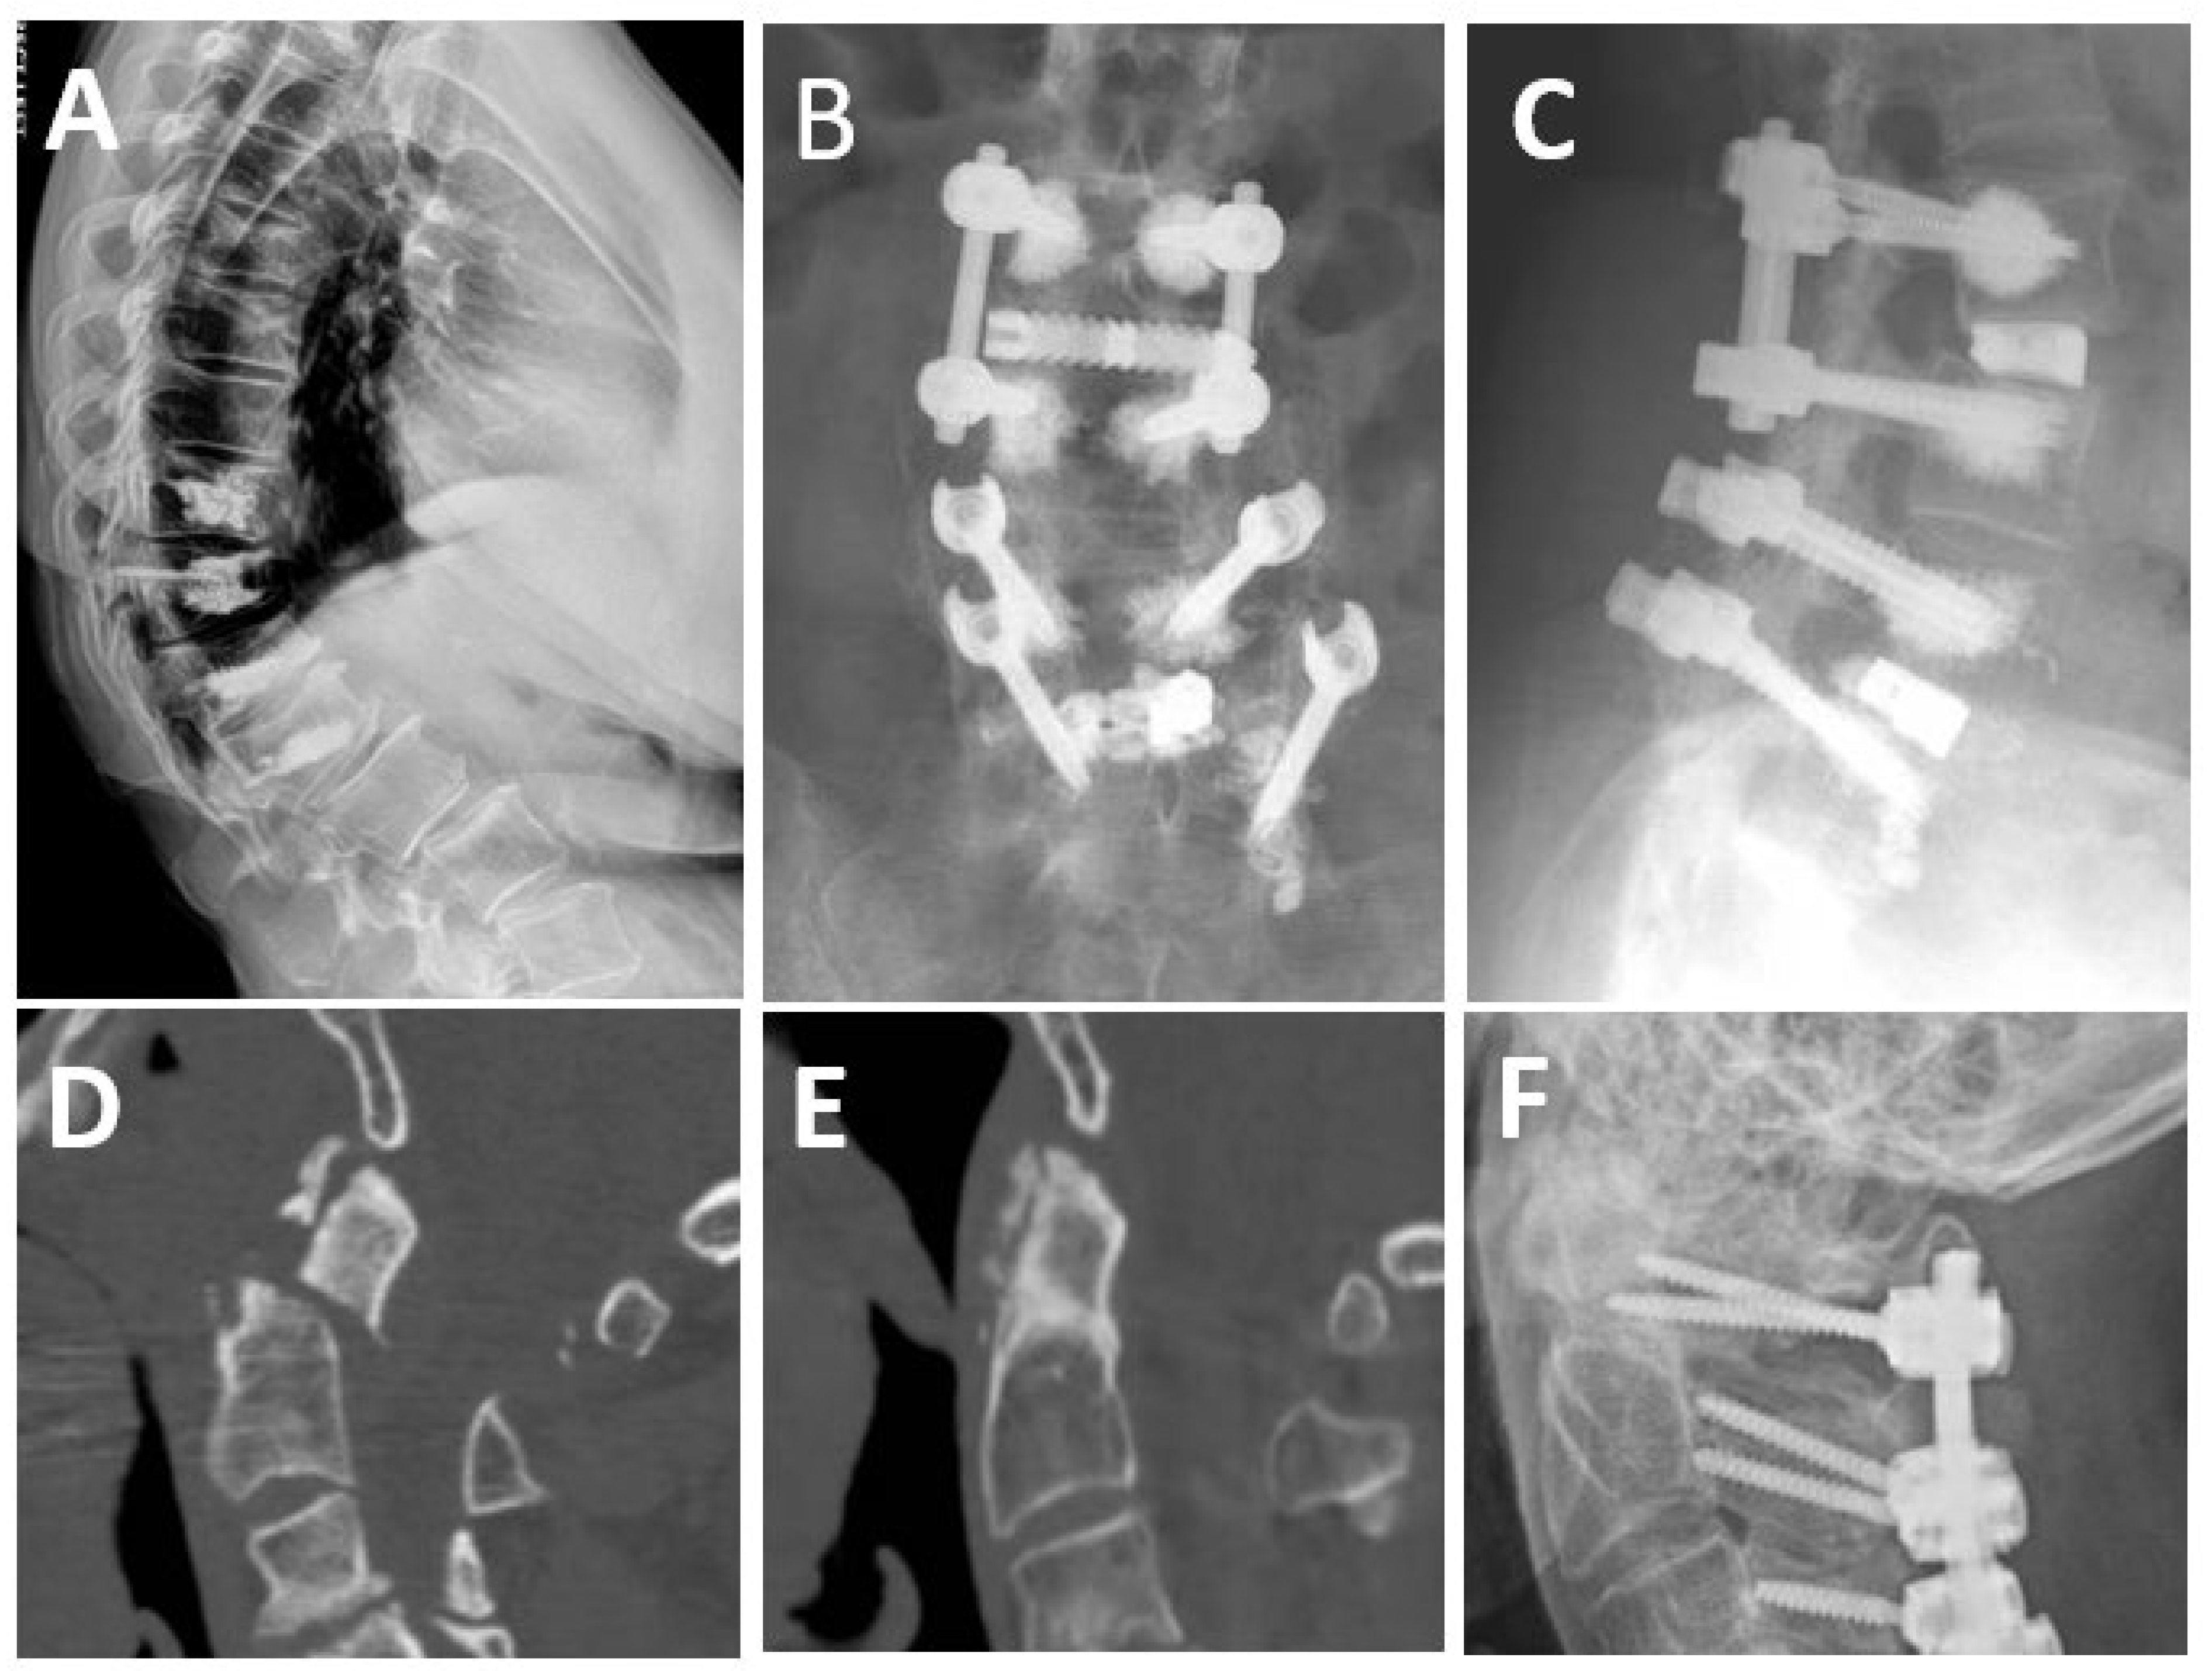

3.3. Proximal Junctional Kyphosis and Failure